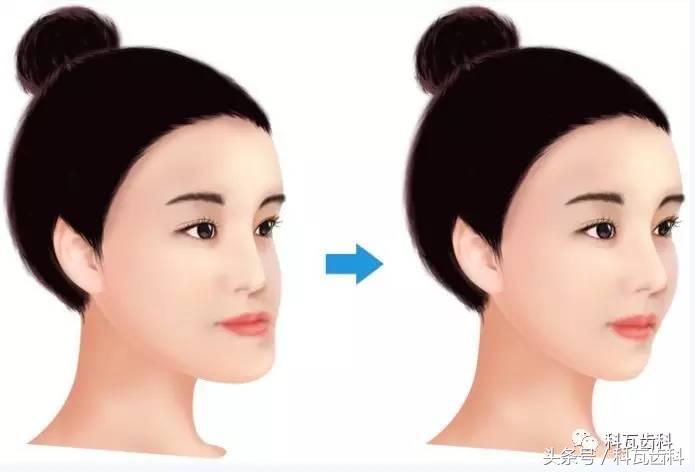

千万别等啊!因为如果放任不管,后你的下巴会越长越大,越长越长。所以呢,小朋友3至5岁就可以找黄医生来看了,越早干预,你将来做手术整形的概率越低,因为反牙合放任不管的结果是像下面这样,现在又叫“香蕉脸”或“月牙脸”。

矫正后 si不si超美的~